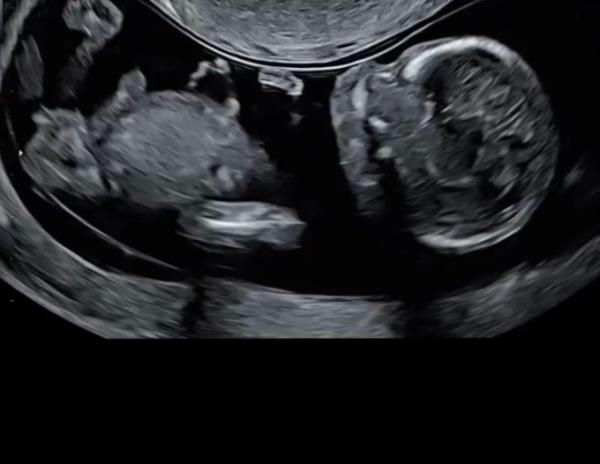

Huhu Mädels, ich war heute bei dem Ersttrimesterscreening. Es ist alles in Ordnung. Bin so happy der Arzt wollte sich nicht äußern zum Geschlecht. Ist ja auch in Ordnung. Am Ende ist man nur enttäuscht wenn es falsch ist. Jetzt sind wir aber trotzdem alle am rätseln und bin so gespannt auf eure Meinung ( dient nur als bespaßung , man kann es vermutlich einfach noch nicht wissen, ICH WEISS)

Man lässt sich ja leicht durch scheinbar ganz offensichtliches verführen - also bin ich für Team blau. Natürlich ohne Gewähr

Ich sag auch ein Bub

Ich sag es ist ein Mädchen LG

Das stimmt Ich war auch sofort Team babyboy